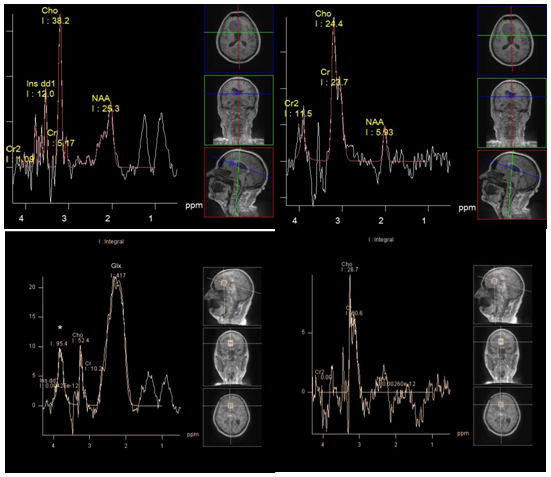

New studies that focus on glutamine/glutamate (2.05 - 2.6 ppm), and glutathione (2.95 ppm) peaks, convincingly demonstrate a high concentration of these metabolites (associated with metabolic cycle of alanine) in meningiomas22,25 (Figure 8). In our studies, all 25 (100%) meningiomas demonstrated a dominant concentration of the glutamine/glutamate complex. Kousi et al.,26 found a typical chemical compounds for meningiomas that can be detected at 3.8 ppm using short TE, as a "distinct peak" (Figure 8). In vitro studies suggest that the "distinct peak" is likely to consist of the sum of resonant frequencies of phosphoethanolamine, alanine, glutamine and glutamate.23 (In our study, in 24 of 25 of meningiomas a "distinct peak" was clearly present).

Figure 8 A typical metabolite profile of meningioma. PRESS TE 30 ms (a), PRESS TE 135 ms (b). Alanine peak (1.5 ppm) partially merge with those of lactate (a,b). The dominant peaks of Glx (a). High choline peak. "The distinct peak" * (a) also can be seen on the spectra, obtained with TE 135 ms at 3.8 ppm (b).

Adenoma, originating from the adenohypophysis does not contain N-acetylaspartate, as well, as other extra cerebral tumors. Chernov et al.,27 describe the "substantial reduction of NAA" in adenomas.27 In our studies, 4 of 5 adenomas showed an evident peak at 2.0 ppm using intermediate TE (in the other extra axial tumors this peak at intermediate TE was absent or barely rose above the noise level). Perhaps, in adenomas this peak corresponds to other N-acetyl compounds, such as N-acetyl glycoproteins (Figure 9). Creatine can be found in a very low concentration or absent.28 The concentration of choline may be relatively high, also sometimes can be observed peaks of lactate and lipids.29

Figure 9 Spectra of pituitary adenoma. PRESS TE 30 ms (a), PRESS TE 135 ms (b) in comparison with suprasellar meningioma. PRESS TE 30 ms (c), PRESS TE 135 ms (d). Peak at 2.0 ppm in the spectra of adenoma, corresponding to NAA resonant frequency, is evident on both short (a) and Intermediate (b) TE. High peak myo-inositol at 3.58 ppm is present (a) there are no peaks of alanine and lactate, and low concentrations of glutamine/glutamate complex (a).